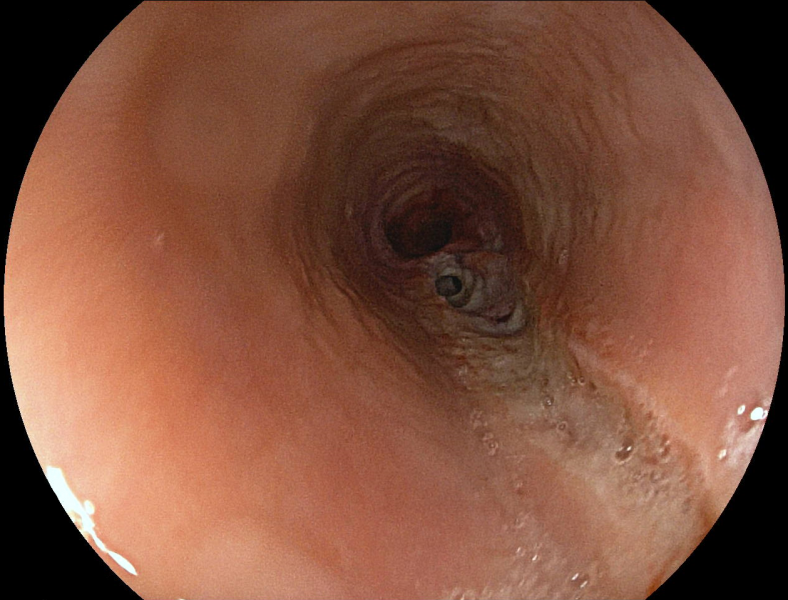

Bone stuck in diverticular ostia of the sigmoid colon: an endoscopic challenge

Fotografia